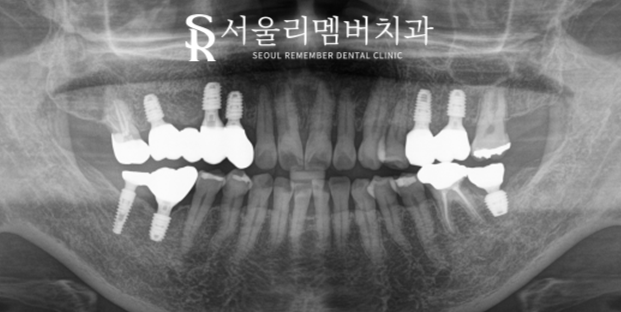

뼈이식 및 모든 식립을 마쳤는데요.

좌, 우측 순서를 나누어 순차적으로 진행했습니다.

모든 과정이 마무리되고 크라운 세팅까지 마쳤습니다.

지르코니아 재료를 사용하여 제작을 도왔는데요.

자연치와 같은 기능, 심미를 재현할 수 있기에

많은 분들이 선호하고 있는 재료 중 하나입니다.